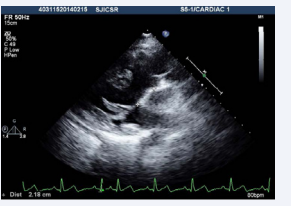

. The echocardiogram showed an elongated left ventricular outflow tract due to subaortic conus (Figure 4, video 5).

Figure 4: Transesophageal echocardiogram long axis view showing presence of subaorticconus with aortomitral discontinuity